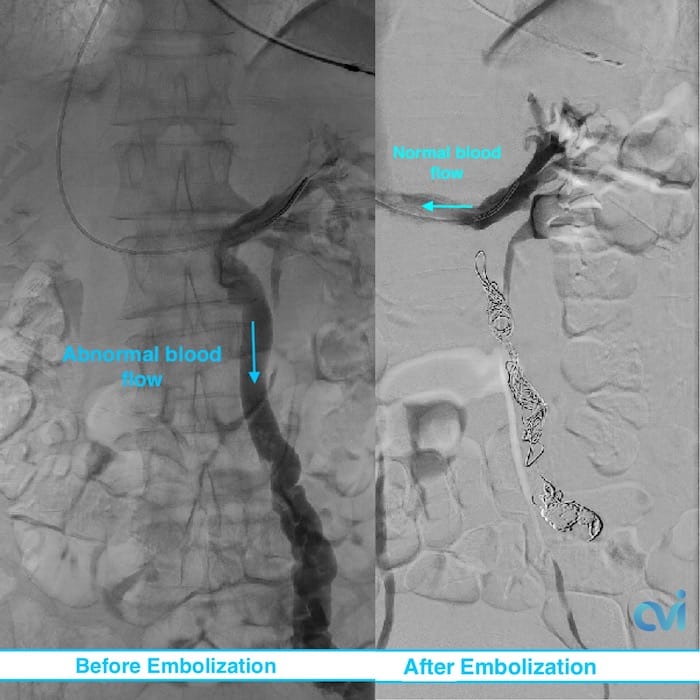

Using x-ray guidance a smaller catheter is then guided into the abnormal ovarian or pelvic veins. The abnormal vein is then treated by placing tiny coils and a specialized fluid causing the vein to seal down. This then restores normal blood flow in the body and improves related symptoms.

Embolization is a safe and effective treatment with minimal downtime and risk. Up to 80% of women report an improvement in symptoms within the first 2-4 weeks after embolization.